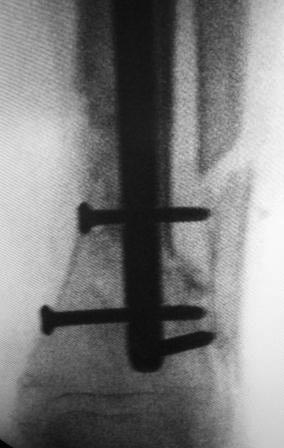

Здравствуйте, уважаемые коллеги! Всем огромное спасибо! Сегодня

оперировали, косая остеотомия н/з малоберцовой кости, открыть зона л/с,

как правильно заметили л/с оказалась не тугая, вообще нет сращения,

интерпозиция м/тканями, к/м канал закрыть частично, сильнейший

остеопороз , даже однозубым крючком всё ломается, экономная резекция

концов, укорочение было 1,5см, стало 3см, дефект заполнили аутографтом,

учитывая что винты не держат пластину не ставили, БИОС реконструктивным

стержнем, дистально 4 винта, два из них через аутокость и оба отломка,

получилось не очень стабильно,  но вроде держится хорошо.

Стержень чуть ушел кнаружу и кпереди--не знаю,  это плохо? Дальше для

стабилизации нужна ли временная внешная иммобилизация?